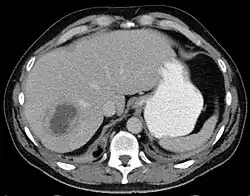

| Liver abscess on axial CT image: a hypodense lesion in the liver with peripherally enhancement. | |